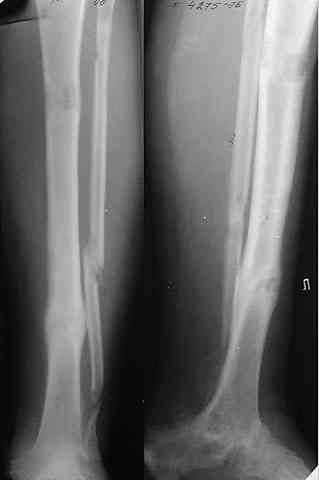

Не адресована другая проблемы - берцово-пяточный блок достигается ценой укорочения конечности на 3-4 см. Поэтому надо предусмотреть что-то для удлинения. У нас в клинике традиционный подход - билокально удлинять большеберцовую кость. Раньше еще и малоберцовую рубили на двух уровнях. Сейчас (спасибо коллегам из форума) пользуемся только

той остеотомией, которая делается для отворачивания кожно-костного лоскута с малоберцовой костью. Фиксируем все это аппаратом (пример в приложении) около 4 мес.

То есть относительно недолго. Про винты поэтому стоит вспомнить, только если опору со стопы хочется снять совсем уж рано. Можно, в принципе, и о штифтовании подумать. Правда, мы пока думаем - они так срастись успевают.

В итоге: мы планируем выполнить пациенту большеберцово-пяточный артродез в аппарате Илизарова с одновременной остеотомией берцовых костей и их последующим удлинением. Возможно, мы дополним фиксацию артродезируемых костей винтами.